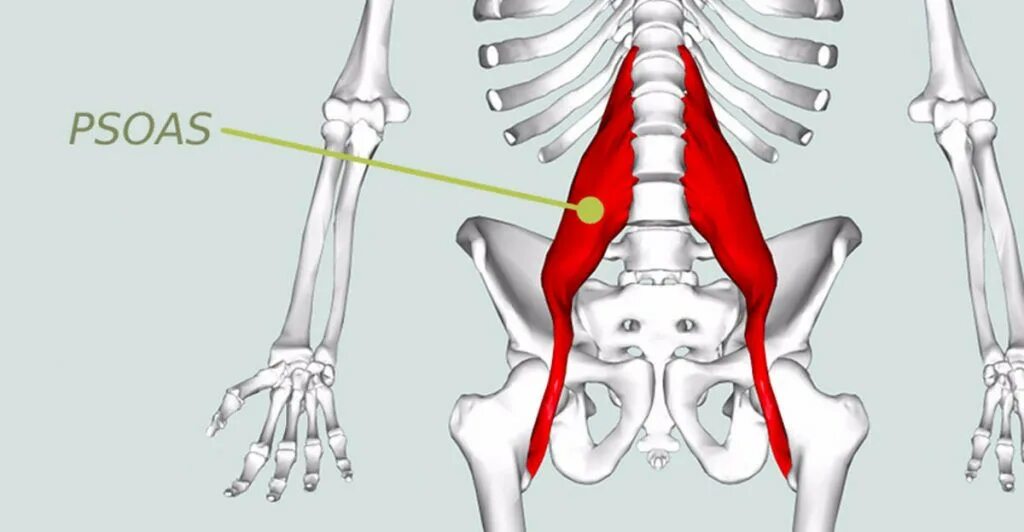

Псоас симптом